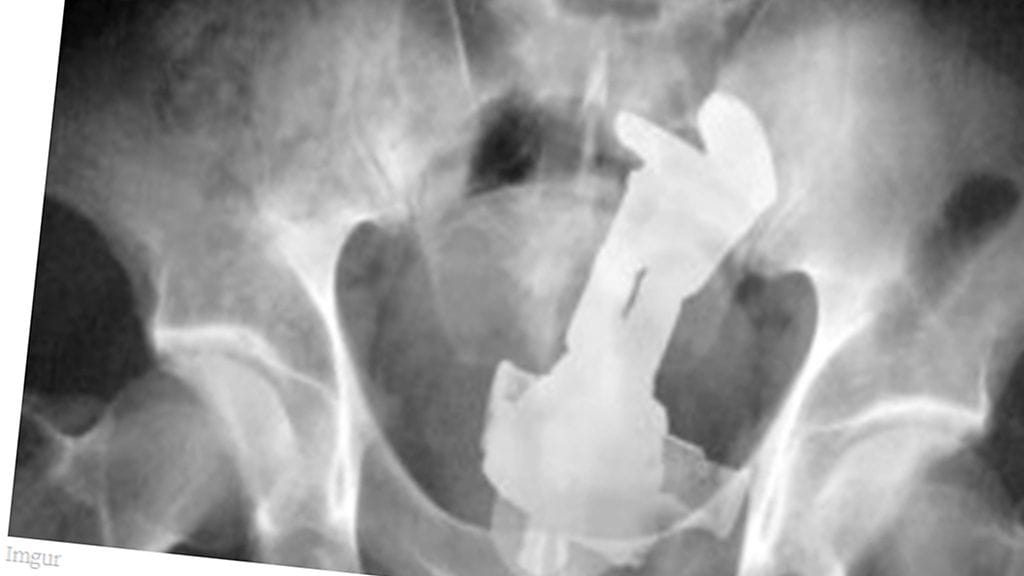

Erikoiset röntgenkuvat saavat ihmettelemään vain yhtä asiaa: voivatko ihmiset oikeasti olla näin typeriä?

Mikä menee sisään, ei välttämättä tule ulos ihan itsestään. Unilad-sivuston julkaisemat röntgen-kuvat asioista, joita himokkaat miehet ovat sisäänsä tunkeneet, eivät ensituntumalta vaikuta edes mahdollisilta.